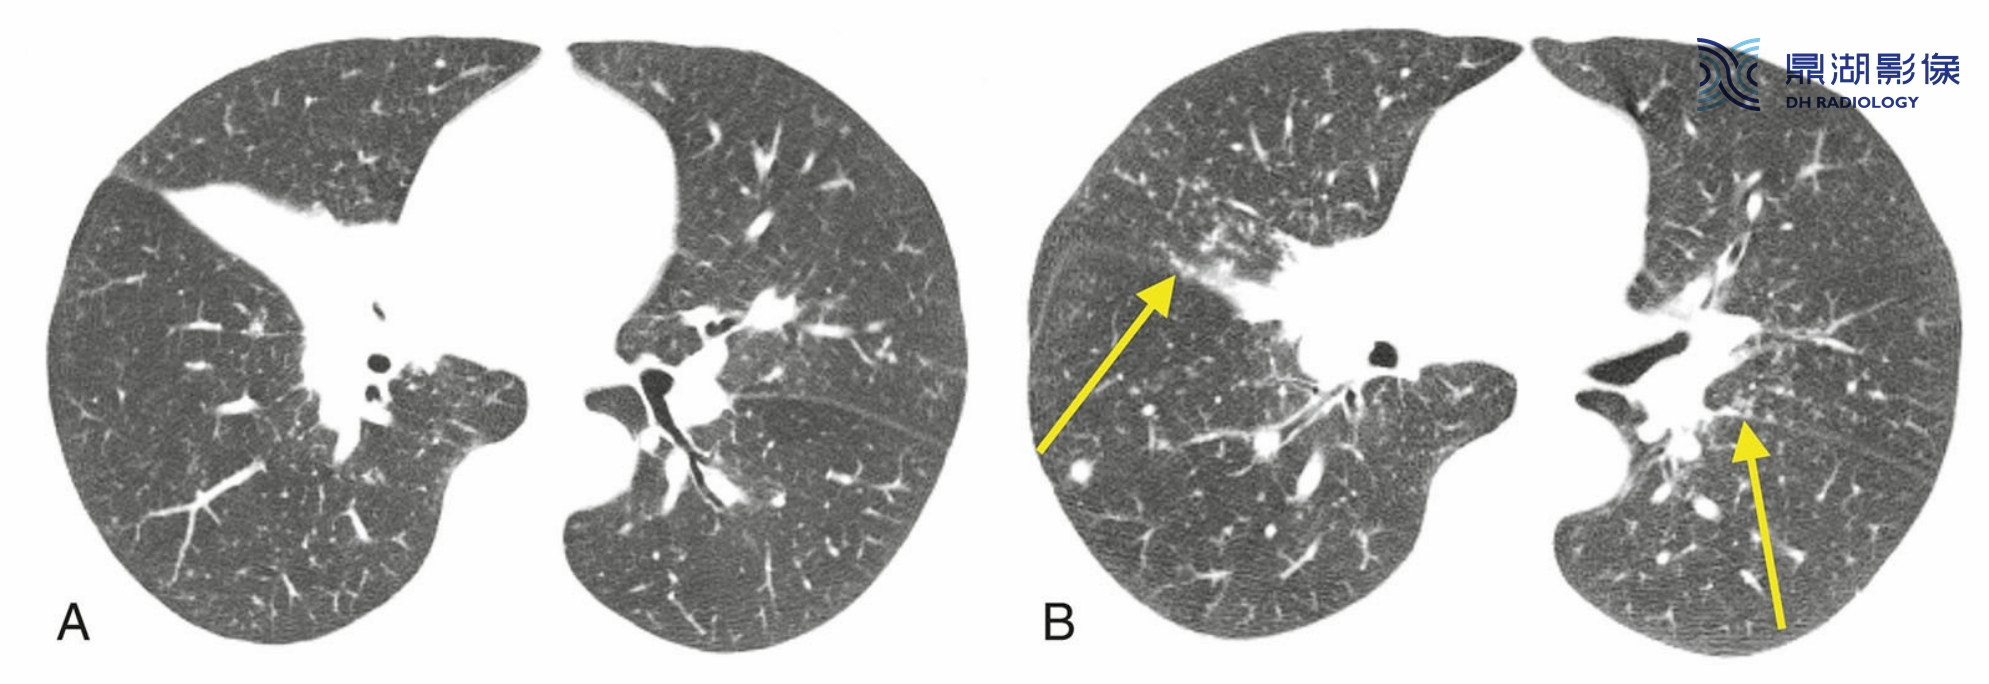

典型结节病伴支气管血管周围和胸膜下结节。

A.HRCT显示肺门区散在的结节,但是与上图相比,其与气管和支气管的关系较难确定。胸膜下结节清晰可见。

B.在较低的层面上,结节数量较少。结节主要分布在上叶,上叶分布是结节病的典型表现。